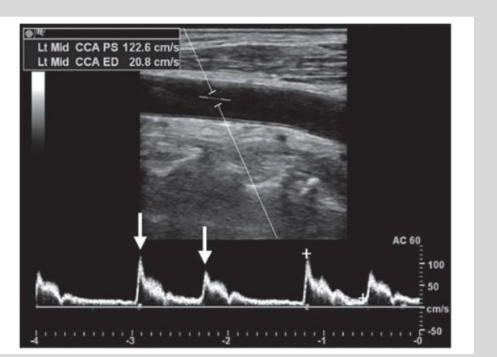

what is this waveform showing?

Bigeminy: irregular beat that

is followed by a normal beat